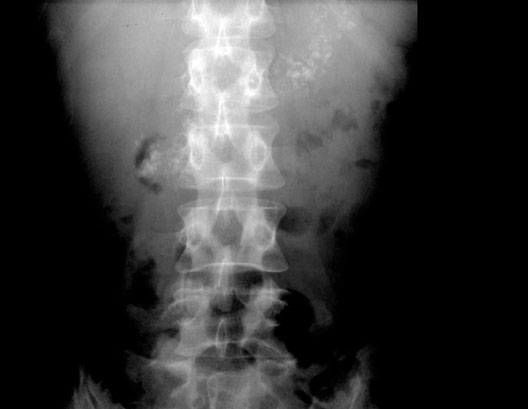

Pancreatic Cancer

Roll mouse over image to display labels.